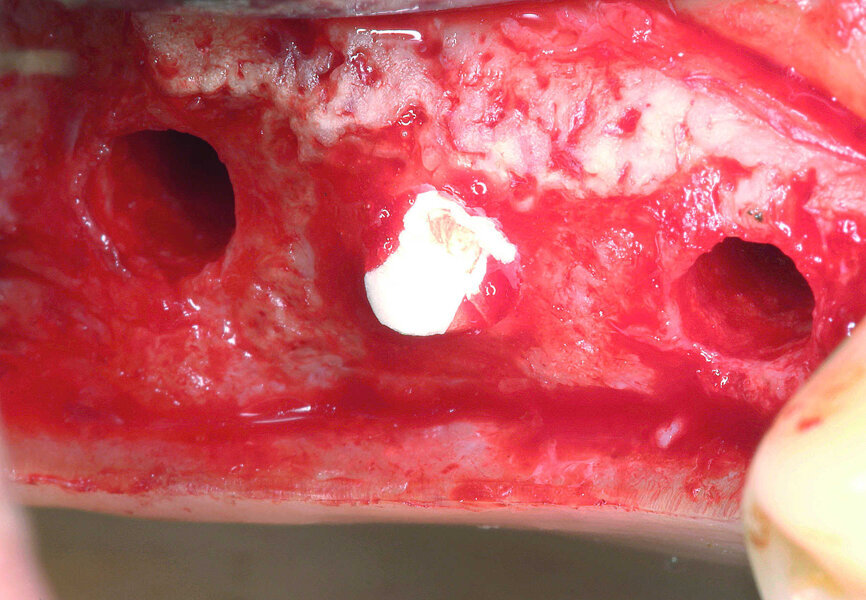

Figs. 10 et 11 : Application d’une membrane de collagène au-dessous de la membrane de Schneider

C’est Tatum, en 1986, qui fut le premier à décrire la technique indirecte d’élévation du plancher sinusien par abord à travers des trous de forage, puis en 1998, Summers a modifié la méthode pour en faire la technique de l’ostéotome telle qu’on la connaît aujourd’hui.3–5 Un examen systématique de la littérature spécialisée a montré que cette approche est prédictible et a peu d’incidence sur les complications peropératoires et postopératoires.6 La fracture du plancher sinusien situé sous le fond des trous de forage a été effectuée à l‘aide d‘un ostéotome (Stoma) adapté au diamètre de forage implantaire (Fig. 9). Grâce à l’utilisation de la technologie Piezon et surtout de curettes angulées miniatures pour sinus, la membrane de Schneider a été constamment maintenue en contact avec l’os et soulevée délicatement sous contrôle visuel (microscope chirurgical). Une membrane de collagène (PARASORB, RESORBA) a été introduite à travers les trous de forage dans la région dentaire 16–17, puis soigneusement appliquée sur le site implantaire, afin de prévenir une perforation de la membrane de Schneider (Figs. 10 et 11). Le filetage a été taraudé pour éviter une surchauffe de l’os pendant l’insertion des implants en zircone dont la conductivité thermique est inférieure à celle des implants en titane (Fig. 12). Des implants (CERALOG Hexalobe, CAMLOG) de 8 mm de long ont été insérés avec un couple de serrage maximal de 35 Ncm contrôlé manuellement, et une vitesse de rotation maximale de 15 tr/min (Fig. 13). Le modèle de connexion du dispositif d’insertion était parfaitement adapté à la zircone. Ce dispositif permet une transmission radiale des forces et il est équipé d’un élément de rupture prédéfini, qui protège contre l’application d’un couple de serrage excessif, et donc contre une pression trop importante susceptible de provoquer des fractures de l’implant ou une nécrose de l’os (Tableau 2).

Le modèle des implants utilisé pour ce cas était favorable à la faible hauteur osseuse existante et écartait de ce fait le risque d’un glissement dans le sinus maxillaire. Les implants en zircone sont fabriqués par un procédé de moulage par injection de céramique (MIC) permettant l’obtention de deux surfaces différentes. La texture de surface dans la zone du col est moins rugueuse que dans la partie endo-osseuse et favorise l’apposition du tissu mou, tandis que la surface endo-osseuse est optimisée pour l’ostéointégration. Les implants ont été insérés en laissant une hauteur supracrestale de 0,5 mm environ, et un couple de 25 Ncm a suffi pour obtenir la stabilité primaire (Fig. 14). Après l’insertion des implants, la membrane de collagène se trouvait en position apicale, tel un écran placé au-dessus des implants de la région dentaire 16–17, qui pénétraient de deux ou trois millimètres dans le plancher du sinus. Un caillot de sang s’était formé dans la cavité créée et favorisait la régénération d’un os stable, grâce à la production de facteurs de croissance durant le processus de cicatrisation des implants.7 Le défaut intra-osseux parodontal au niveau de la dent 18 a été comblé avec un phosphate tricalcique bêta pur (Fig. 15).